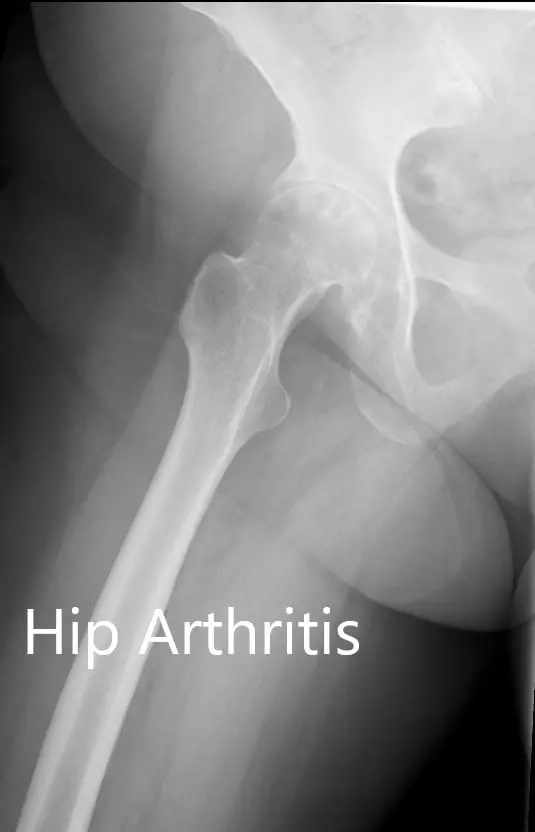

There was no distal neurological deficit. The distal extremity pulses were good volume and palpable. There was a linear scar over the right knee consistent with a previous right knee replacement. Imaging studies revealed severe osteoarthritis of the right hip.

Preoperative X-ray showing the AP and the frog-legged lateral view of the right hip